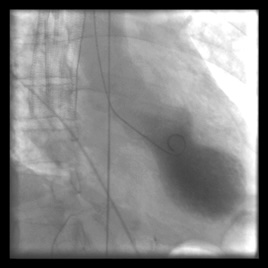

Stress Cardiomyopathy (Takotsubo Cardiomyopathy)

- Also known as:

- “Broken Heart Syndrome”

- “Apical Ballooning Syndrome”

- Aetiology:

- Emotional or physical stress

- Catecholamine surge → coronary vasospasm and myocardial stunning

- Pathogenesis:

- LV apex balloons while the base remains hypercontractile → classic “octopus trap” shape

- Investigations:

- ECG: ST elevation

- Raised troponins

- CXR and echocardiogram: regional wall motion abnormalities

- Serum catecholamines